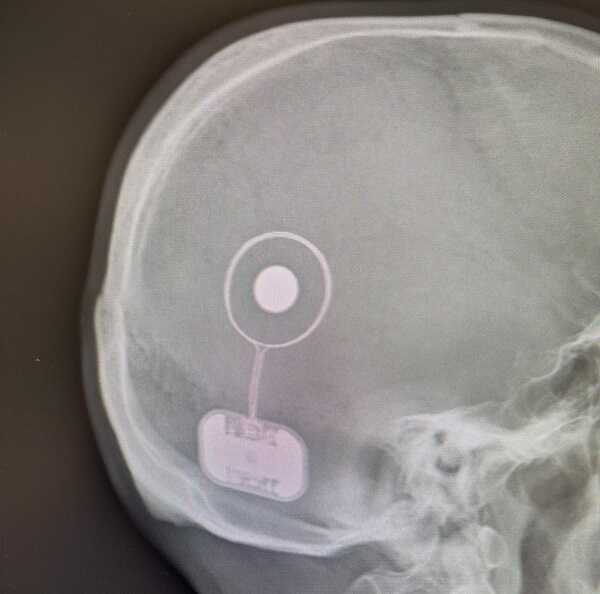

Il dr. Frezza ha utilizzato il recente impianto, dopo aver frequentato un corso specifico a Goteborg, in Svezia, assieme ad altri tre colleghi italiani e una selezione di altri cinquanta otochirurghi a livello mondiale: “L’impianto in questione viene collocato sotto la cute , con un intervento in anestesia generale, della durata di circa quaranta minuti. Il sistema utilizzato è il primo impianto attivo osteointegrato stabile del mondo progettato per il trattamento delle sordità di tipo trasmissivo e misto – spiega il dr Frezza -. Si posiziona posteriormente al padiglione auricolare ed è costituito da un processore esterno, delle dimensioni di una moneta da due euro, del colore dei capelli del paziente, che elabora i suoni ambientali e li trasmette attraverso un collegamento digitale a una parte interna sottocutanea che genera la stimolazione uditiva come vibrazione meccanica. Il componente impiantato – continua -, integrato nell’osso tramite una piccola vite in titanio, contiene la parte attiva del sistema e utilizza la tecnologia piezoelettrica per generare le vibrazioni che bypassano le aree bloccate del sistema dell’udito naturale. Il processore esterno, attraverso la connettività smart-wireless, può essere controllato con una app da telefoni compatibili e interagire con telefonino, televisore, stereo, e altre funzioni”.